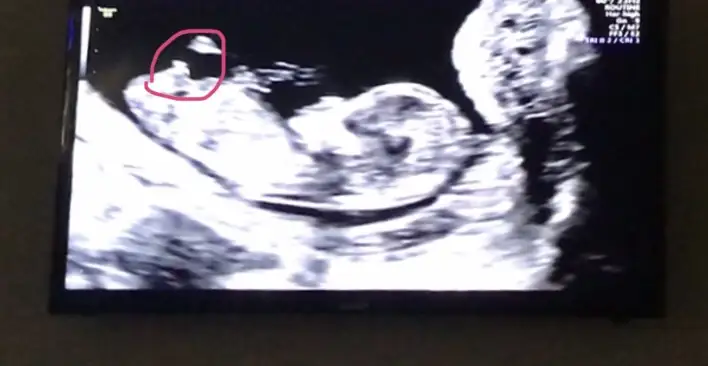

☺️☺️ mouse ile gösterdi hatta mouse’nin oku var orda görebiliyor musunuz bilmiyorum. Buda pipisi diye üstüne basa basa söyledi. Sürekli delikanlı diye muayeneye devam etti🤣🤣 ben Videoya çektim videodan aldım fotoğrağrafı. Sonraki muayenede artık nub olmıcak bakalım kız mı erkek mi? Çok teşekkür ederim size. Sonucu yazarım buraya

Yordum sizi🙈 hakkınızı helal edin. Ben videodan bir kaç fotoğraf daha ekledim. Tekrar bi bakabilirseniz çok sevinirim🌸🌸